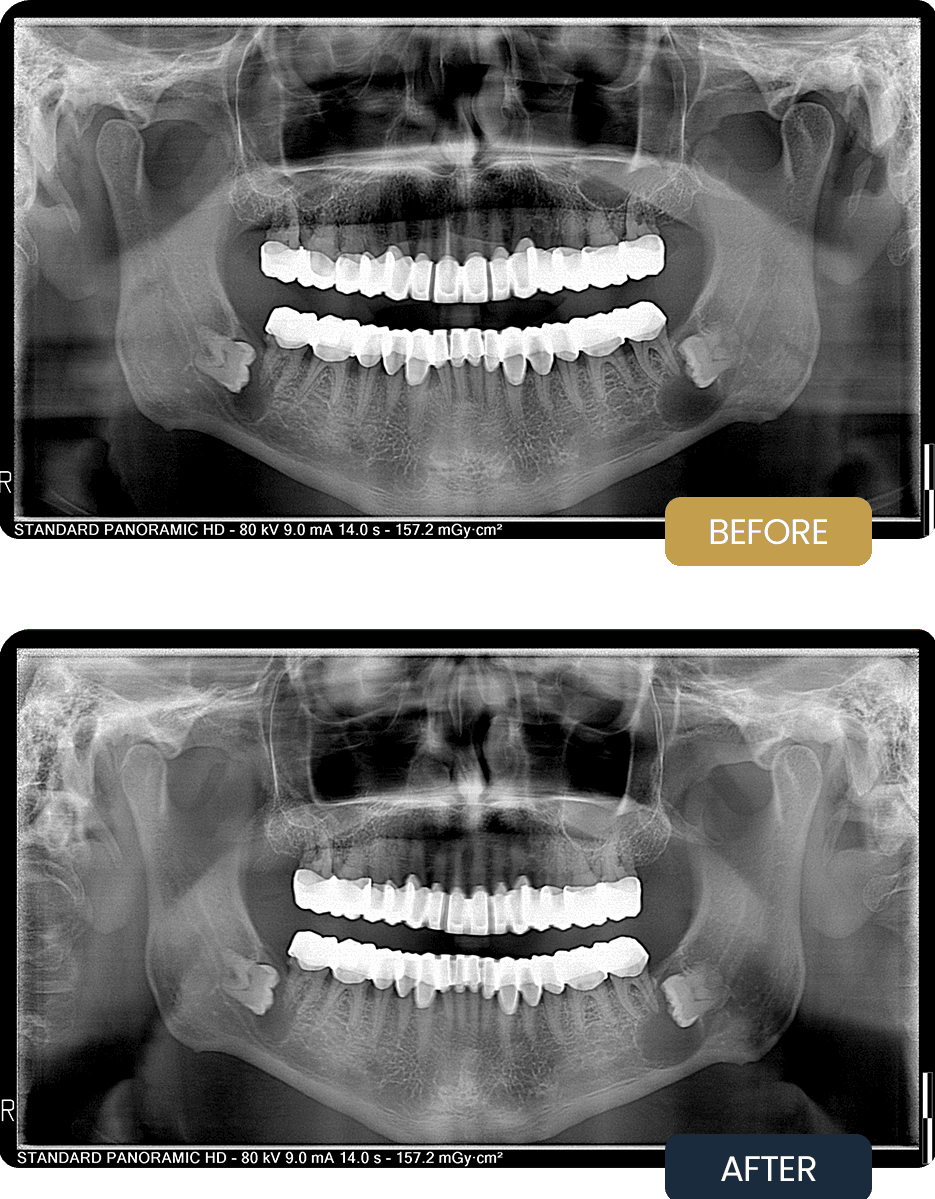

At presentation, Ashley reported discomfort and functional issues related to the upper jaw. Radiographic evaluation confirmed the presence of full arch zirconium crown restorations in both arches, with visible fractures affecting several upper crowns.

The pre treatment panoramic image demonstrates the compromised condition of the upper restorations prior to aftercare intervention, highlighting the need for prosthetic correction and occlusal adjustment.

Post treatment panoramic imaging confirmed stable, well seated zirconium crown restorations across both arches, with repaired and replaced crowns in the upper jaw. Improved occlusal alignment and crown integrity were observed.

Following treatment, Ashley regained comfortable chewing function and enhanced prosthetic stability, supported by a structured aftercare approach focused on longevity and maintenance.